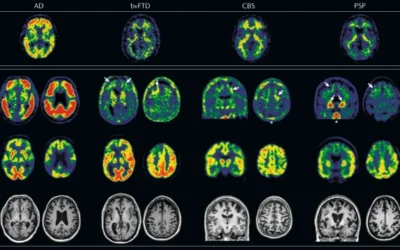

An update on blood-based biomarkers for non-Alzheimer neurodegenerative disorders.

Ashton NJ, Hye A, Rajkumar AP, Leuzy A, Snowden S, Suárez-Calvet M, Karikari TK, Schöll M, La Joie R, Rabinovici GD, Höglund K, Ballard C, Hortobágyi T, Svenningsson P, Blennow K, Zetterberg H, Aarsland D. Nat Rev Neurol. 2020 May;16(5):265-284. doi:...